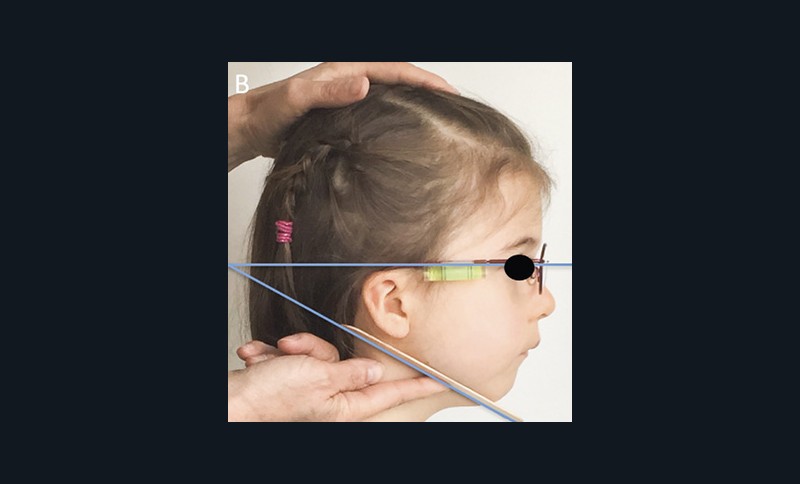

Examen exobuccal

L’examen clinique orthodontique débute par un examen exobuccal de face et de profil qui permet à l’orthodontiste d’identifier certains signes d’appel du Sahos [4]. L’examen de face apprécie la forme globale du visage, la typologie et la symétrie faciale (fig. 5). Des signes caractéristiques sont souvent rapportés chez les enfants suspectés de Sahos : incompétence labiale au repos, hypotonie de la lèvre supérieure avec un angle naso-labial augmenté, visage allongé, orifices narinaires étroits et pincés et présence de cernes (fig. 6a) [5]. Ce sont des indicateurs indirects d’une obstruction ou d’un rétrécissement nasal et d’une ventilation buccale [5-6].

L’examen de profil apprécie les rapports maxillo-mandibulaires et la convexité du visage dans le sens antéropostérieur. Chez les enfants apnéiques, on note généralement la présence d’un profil convexe rétrusif avec un menton en retrait, associé à des dépôts graisseux si l’enfant est en surpoids. Une hypotonie de la lèvre supérieure, qui se traduit par un angle naso-labial ouvert, signe d’un hypo-développement maxillaire, est souvent présente [7]. Enfin, on observe parfois une contraction du muscle mentonnier associée à une occlusion labiale forcée (fig. 6b).